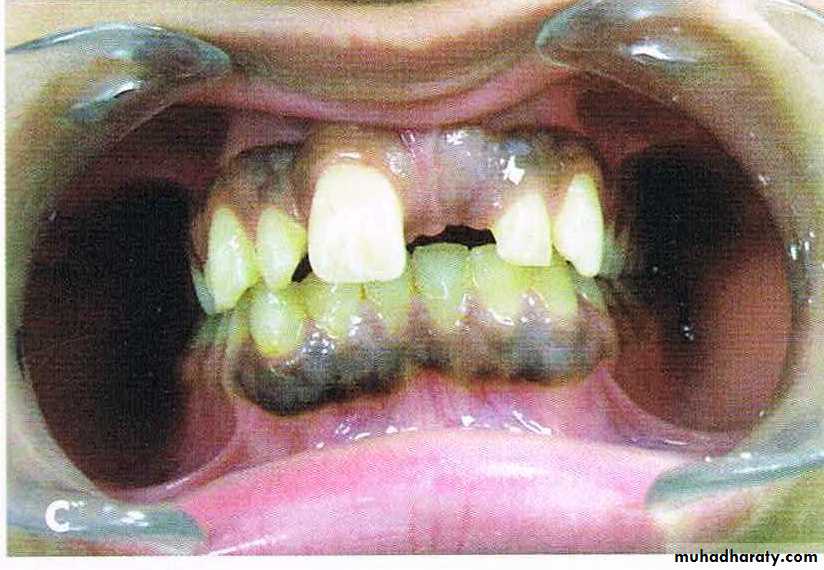

Bimaxillary protrusion

Bimaxillary proclination: the teeth are proclined on normal bases

Bimaxillary protrusion or bialveolar protrusion refers to a protrusive dentoalveolar position of maxillary and mandibular dental arches that produces aconvex facial profile .Bimaxillary prognathism: the jaws/basal bones are forward relative to the cranial base

Features

• Soft tissue• Convex facial form.

• Reduced lip length.

• Lips incompetency.

• Low lower lip line and high upper lip line

• prominent lips.

• Receded chin.

• Dental

• Dental bimaxillary proclination• Larger dental arch length with resultant spacing and diastema

• Normal or increased OJ

• Variable molar relationship but usually normal.

• Large teeth compared to normal population

• May have other superimposed malocclusion

Before & After Treatment